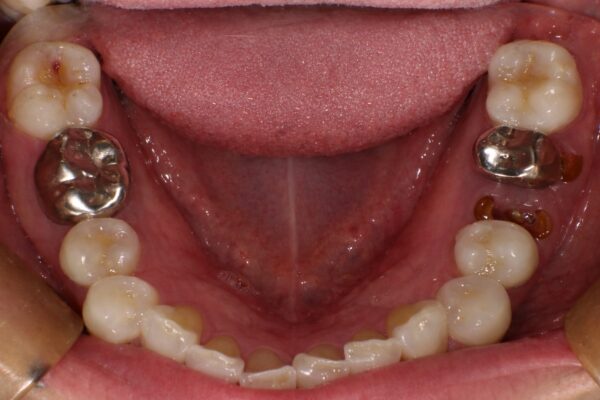

Images